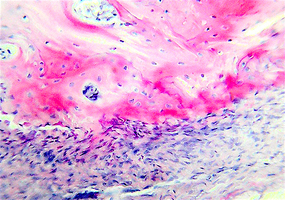

1. Очистка и обработка материала. Получение биоиплантата "Лиопласт"

2. Поверхность и структура материала для изготовления биоимплантатов